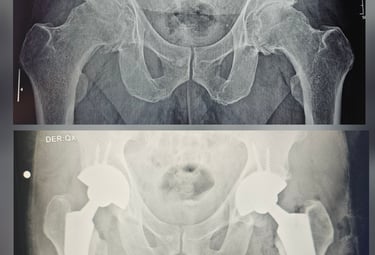

Cirugía Articular

Realizamos procedimientos quirúrgicos avanzados para mejorar la calidad de vida de nuestros pacientes. Nuestros equipos médicos están altamente capacitados y utilizan tecnología de vanguardia para asegurar los mejores resultados posibles. Cada paciente recibe atención personalizada, con un enfoque en sus necesidades específicas y un seguimiento continuo para garantizar su bienestar a largo plazo.